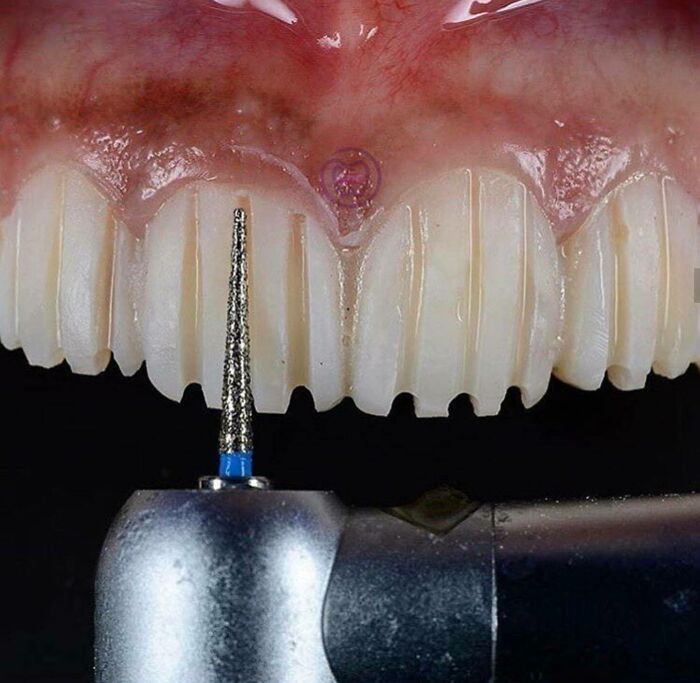

Cabezas de muñecas Barbie cortadas en la antena de un coche. Un campo de césped cubierto de tenedores de plástico. Un tipo prendiendo fuego a su pelo. No hay nada más cautivador que ver una imagen en Internet que nos deja un poco sin palabras y mucho más confundidos. Puede que no tengamos ni idea de dónde han salido estos escenarios malditos, pero hay una cosa que todos tienen en común. Nos hacen sentir muy incómodos.

"La 'imagen maldita' es un fenómeno de Internet", dijo a Bored Panda el doctor Frank T. McAndrew, profesor de psicología en el Knox College. "Es una imagen que resulta inquietante porque hay algo que no está del todo bien en ella, pero a menudo no podemos precisar exactamente por qué es tan perturbadora".

"Puede combinar cosas que no deberían ir juntas (¿una tarta de cerezas con una cara humana ensangrentada horneada en ella?) o presenta un objeto en un contexto al que no pertenece", continuó el profesor. En cuanto a por qué nos hacen sentir incómodos, explicó que no nos gusta la incertidumbre. "Nos gusta dar sentido al mundo que nos rodea, y las cosas que desafían nuestras expectativas o las que son difíciles de categorizar nos sacan de nuestro juego".

Sin embargo, muchas personas disfrutan viendo esos escenarios espeluznantes mientras se desplazan sin pensar por sus redes sociales. "Las personas que son tolerantes a la ambigüedad o están abiertas a nuevas experiencias pueden sentirse atraídas por ellos porque ofrecen una distracción agradable de la normalidad y nos presentan un rompecabezas cognitivo que resolver", añadió, diciendo que otros simplemente los encuentran desagradables.

"Estamos programados por la evolución para centrarnos intensamente en las cosas inesperadas o inusuales de nuestro entorno. Es esencial determinar si esas cosas suponen algún tipo de amenaza para nosotros o no, y las imágenes malditas acaparan la parte de nuestro cerebro encargada de protegernos", señaló McAndrew.

"Las imágenes clásicas son confusas y un poco inquietantes porque no puedes saber realmente lo que está pasando en ellas, y la mente de la gente intenta rellenar los espacios en blanco", explicaron. "Creo que asustan a algunas personas de la misma manera ambigua que la gente tiene miedo a la oscuridad; no entienden lo que se les oculta".